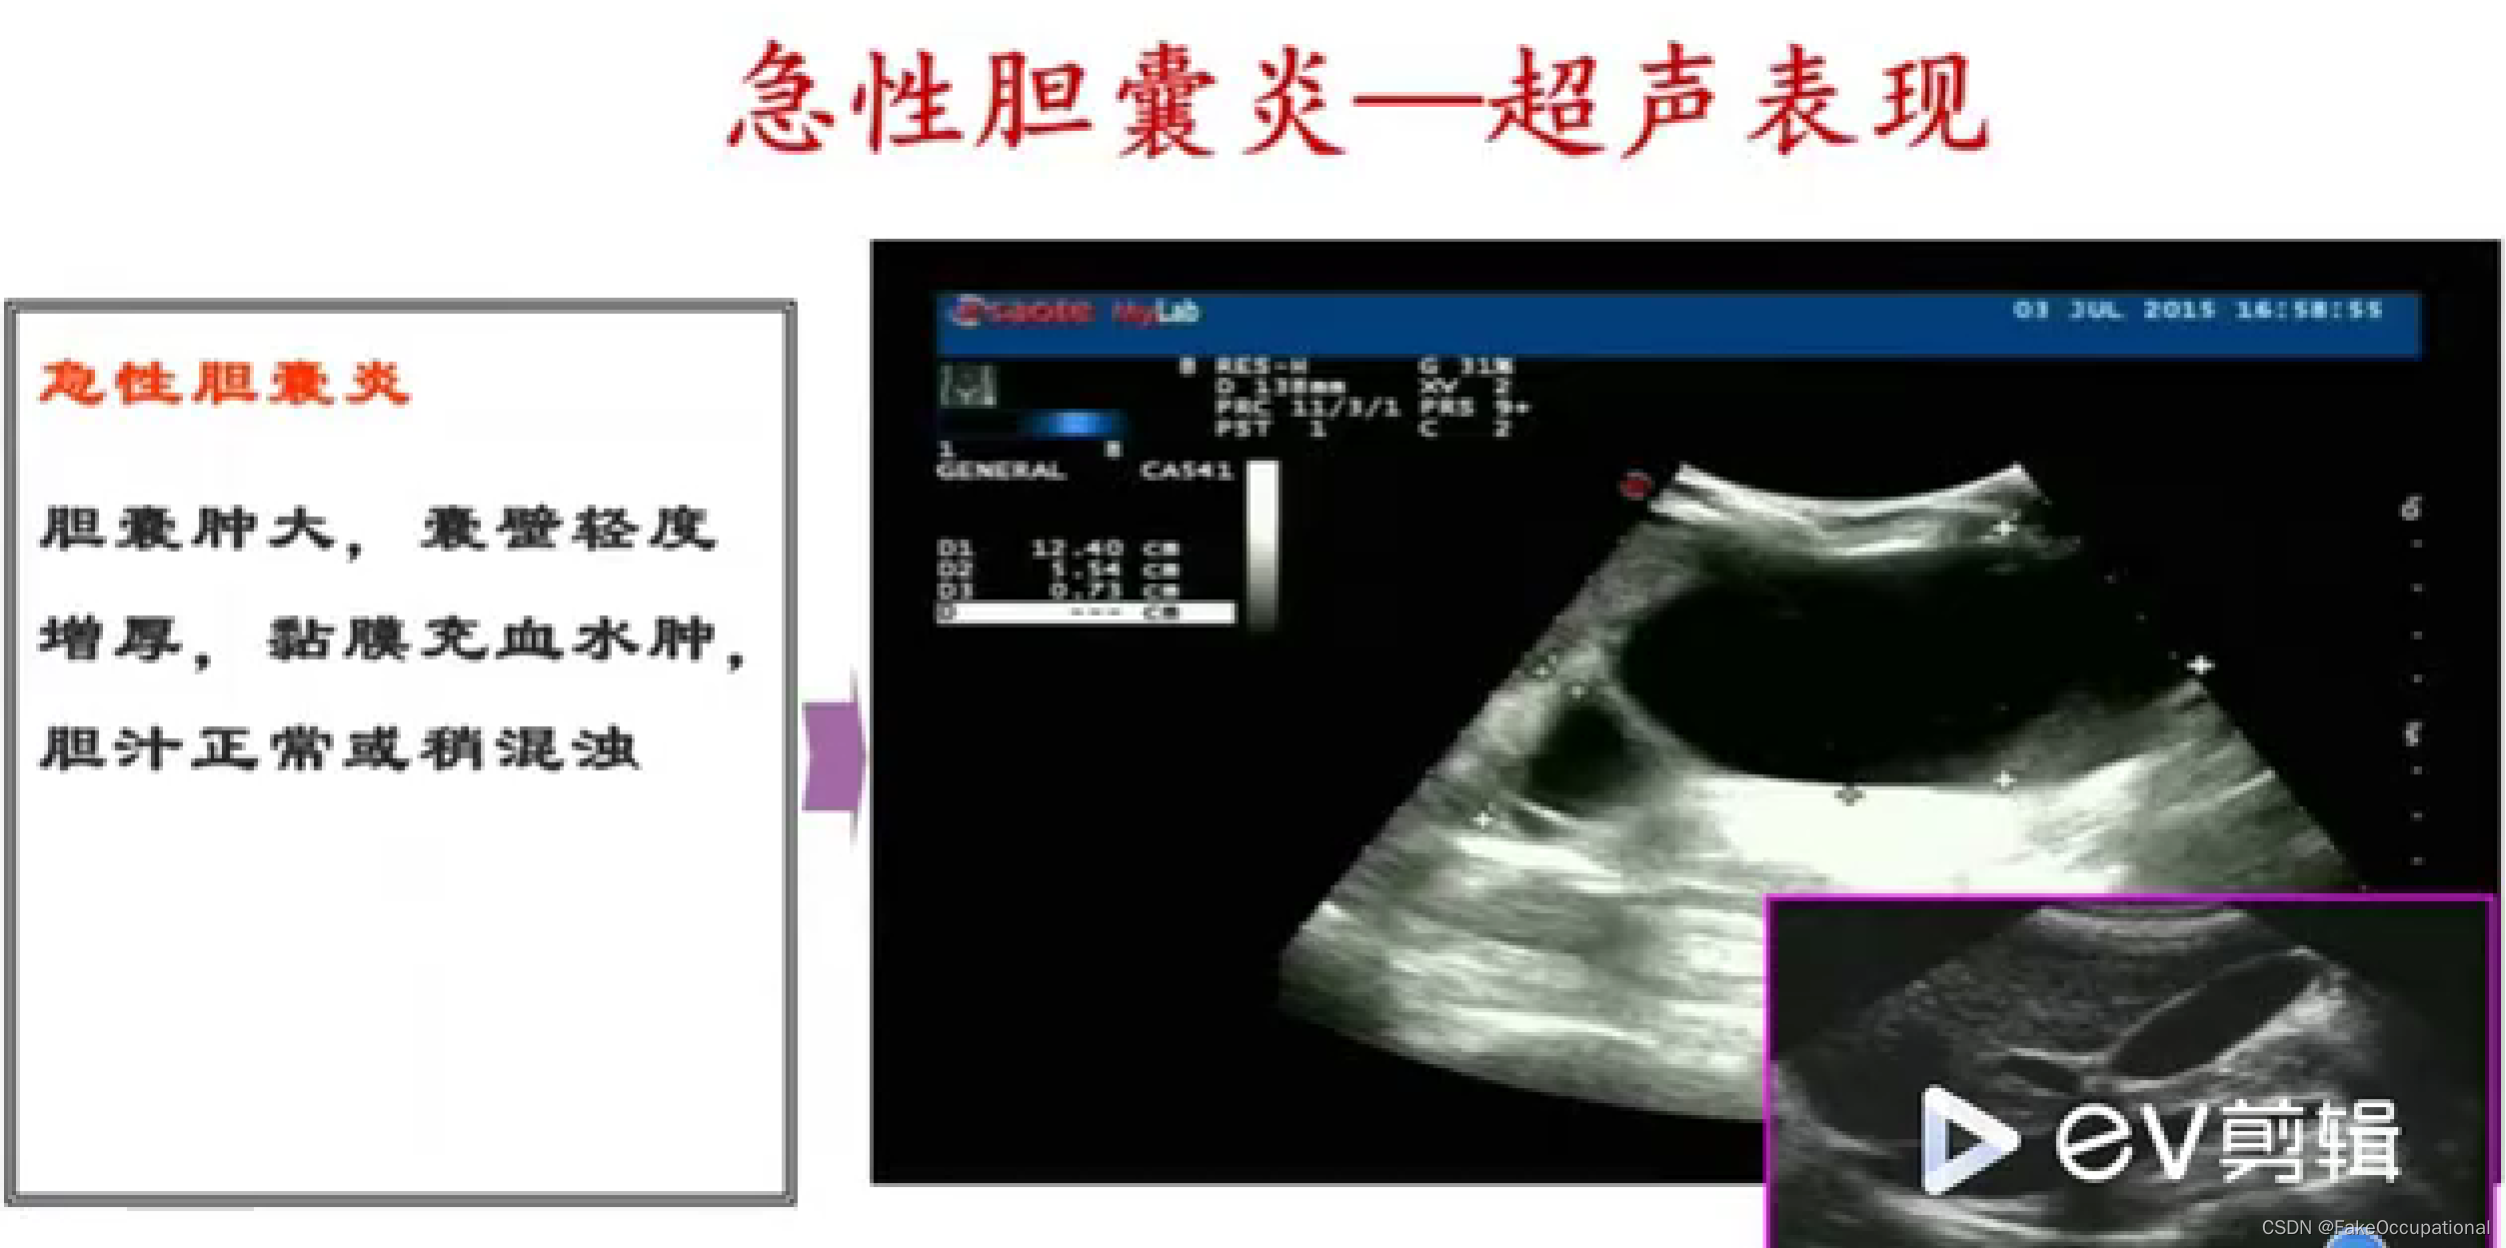

异常胆囊及胆管声像图